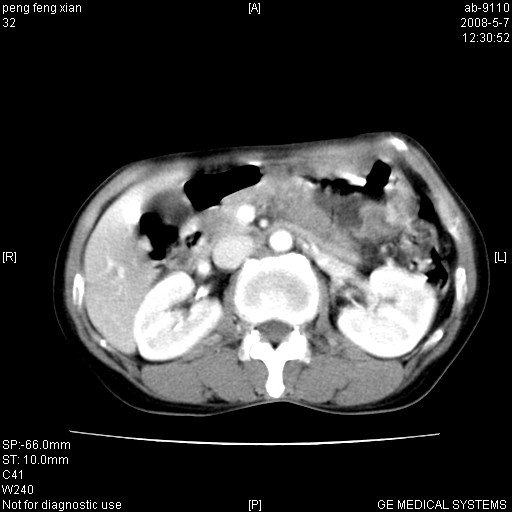

女,56岁。b超左一腹包块,考虑胃肠道肿瘤。

考虑为:胃肿瘤(胃癌?)。建议:行胃镜检查进一步明确诊断。

胃壁增厚,左前胸壁局限性隆起,考虑胃癌可能性大,建议做胃镜

典型胃癌胰体尾部受侵。

胃体部胃壁增厚,不均匀性强化,与胰腺分解欠情.

考虑:胃癌,胰腺受侵待除外.

鉴别:胃淋巴瘤(强化不明显)

建议:胃镜检查.